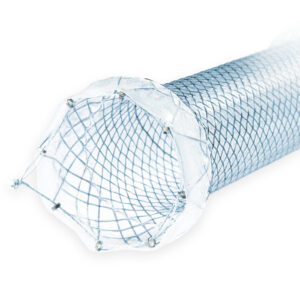

With covering, double-cup |

With covering, double-cup |

With covering, double-cup |

With covering, double-cup |

With covering, double-cup |

With covering, double-cup |

With covering, double-cup |

With covering, double-cup |

With covering, double-cup |

With covering, double-cup |